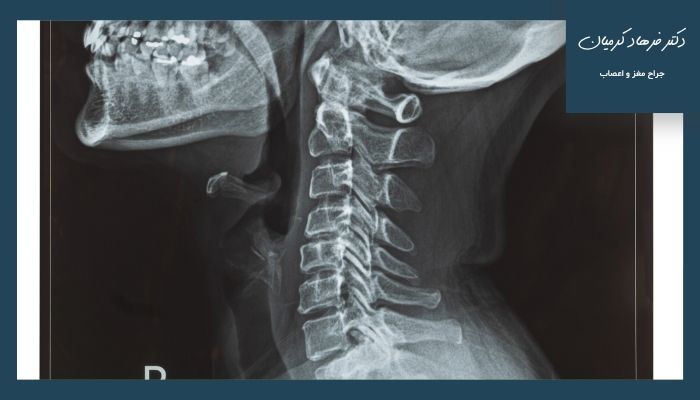

مقایسه آرتروز گردن و دیسک گردن

آرتروز گردن یا “اسپوندیلوز گردنی” نوعی بیماری تحلیلبرنده مفصلهای گردن است که در اثر فرسایش و تخریب غضروفهای بین مهرههای گردنی بروز میکند. این فرآیند معمولا با افزایش سن رخ داده و منجر به کاهش فضای مفصلی، ساییدگی استخوانها و ایجاد استخوانهای زائد (استئوفیت) میشود.دلایل آرتروز گردن:

دیسک گردن به فتق یا بیرونزدگی دیسک بین مهرهای گردنی اشاره دارد. دیسکها ساختار بالشتی بین مهرهها هستند که با افزایش فشار پارگی یا تحلیل رفتن قسمت داخلی ژلهای دیسک از محل خود خارج شده و روی ریشه عصبی گردن فشار میآورد.دلایل دیسک گردن: